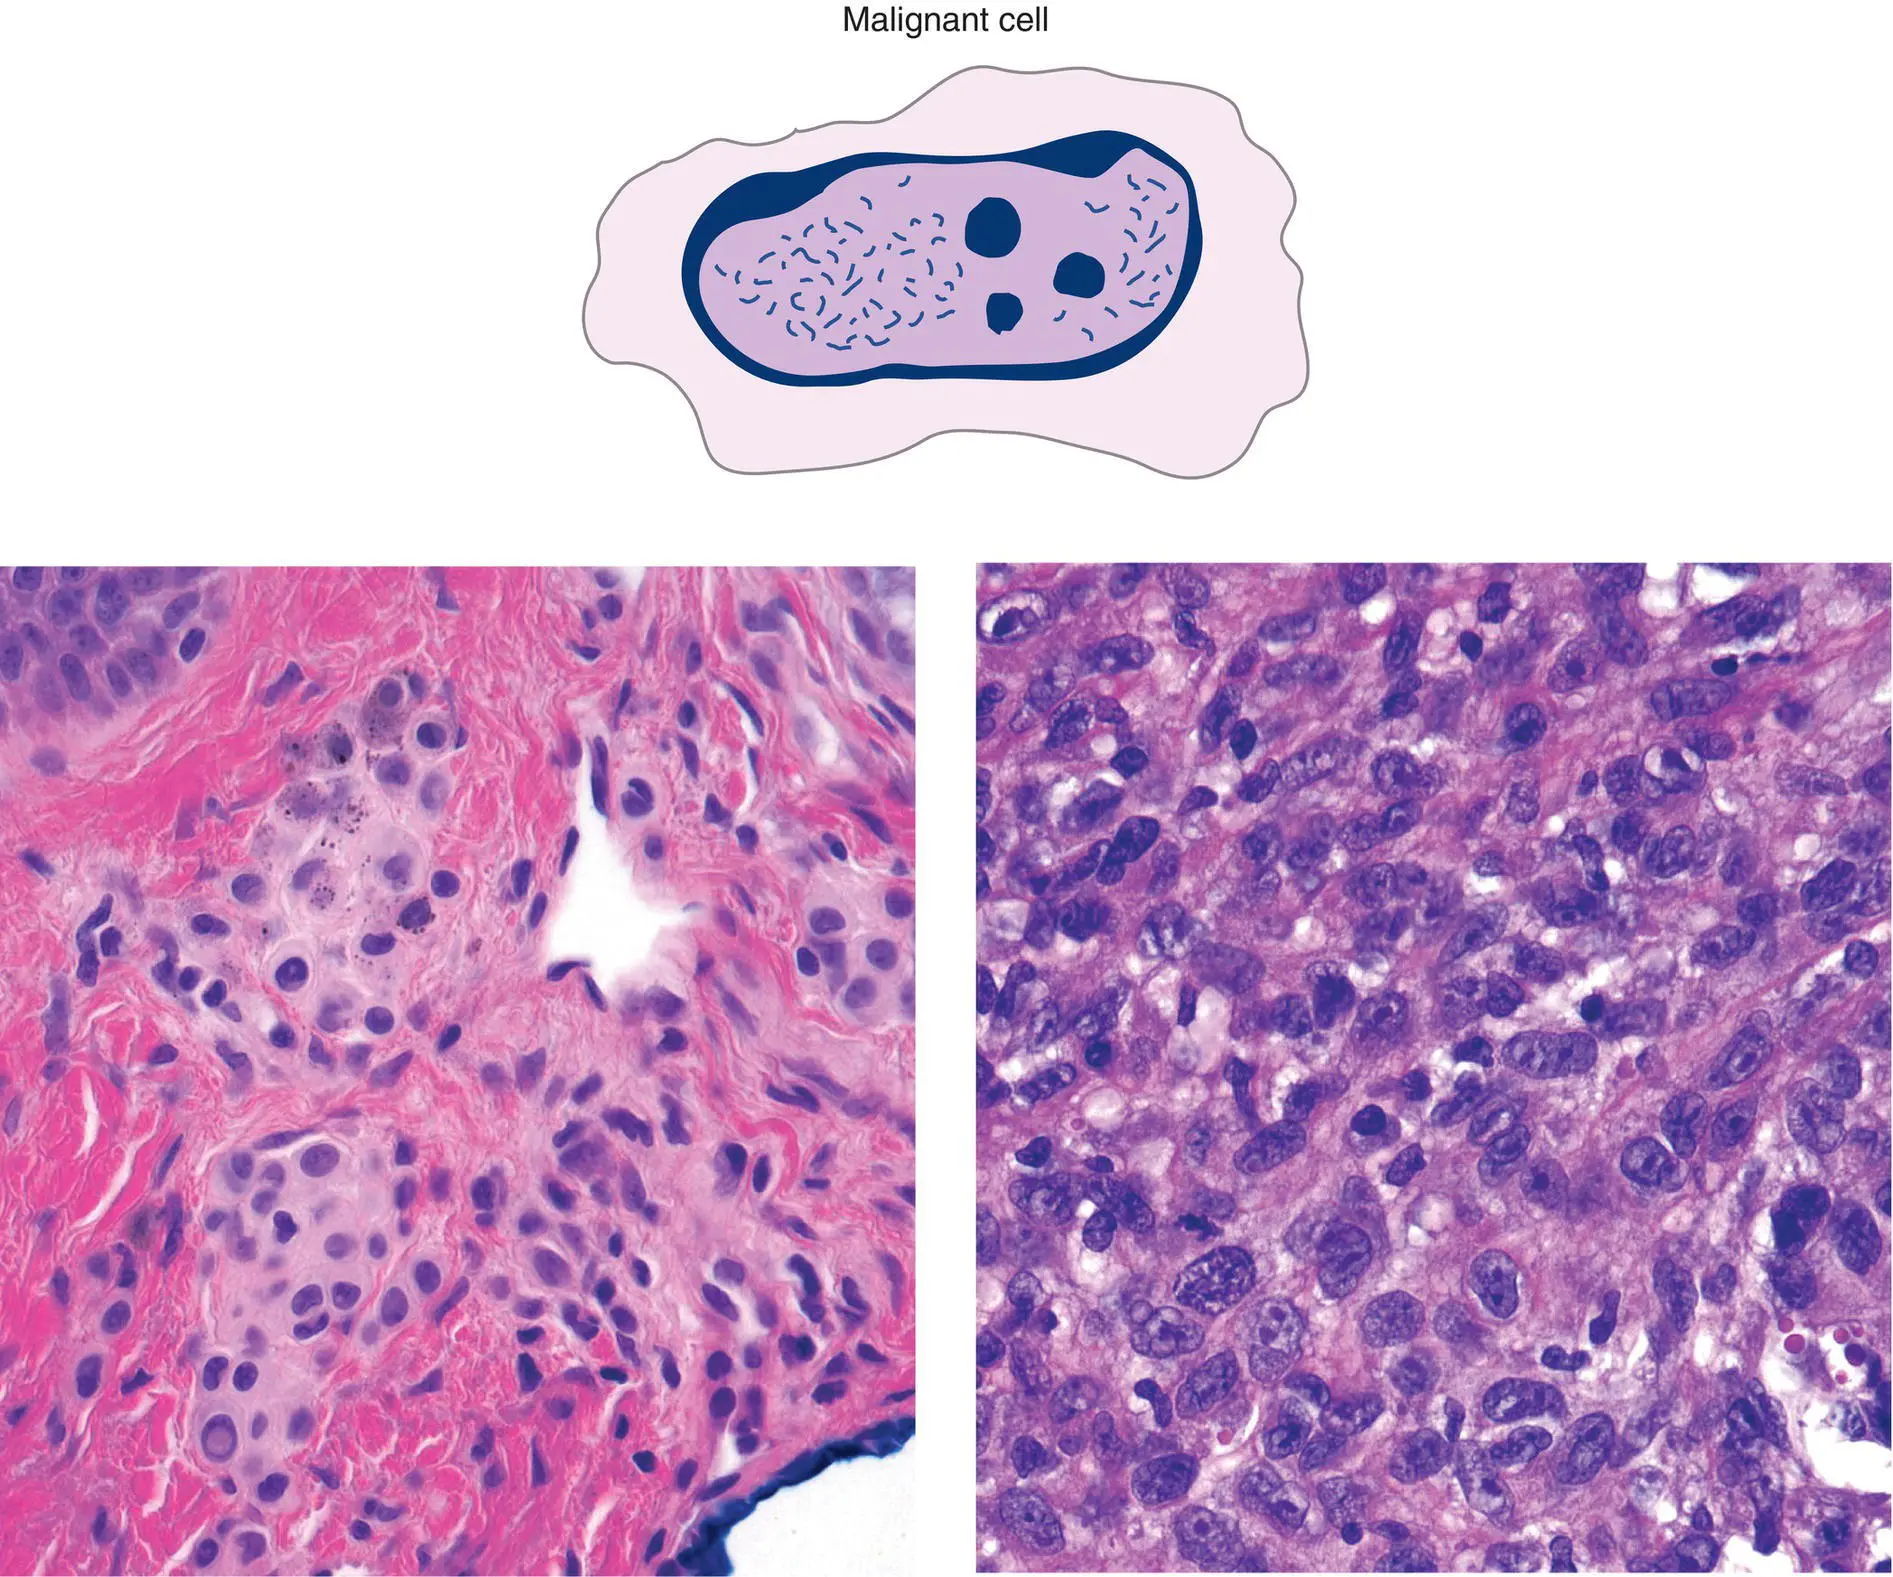

Figure 2(D)Cytologic features are important in pointing toward a benign versus malignant tumor

Malignant cells have high nuclear:cytoplasmic ratio, irregular chromatin pattern, irregular nuclear contours, irregular nucleolar shape and size

Primarily nuclear details suggest cytologic malignancy

Cytoplasmic features point to differentiation: keratinocytes – eosinophilic, hyalinized cytoplasm, melanocytes – fine brown pigment

| Benign nevomelanocytes (left) |

versus |

Melanoma cells (right) |

| Small nucleus, abundant cytoplasm |

|

Large nucleus, relatively little cytoplasm |

| Smooth nuclear border |

|

Irregular nuclear border |

| Chromatin pattern nondescript |

|

Irregular, chunky nuclear contents (chromatin) |

| Inconspicuous nucleolus |

|

1 or more large, purple nucleoli |